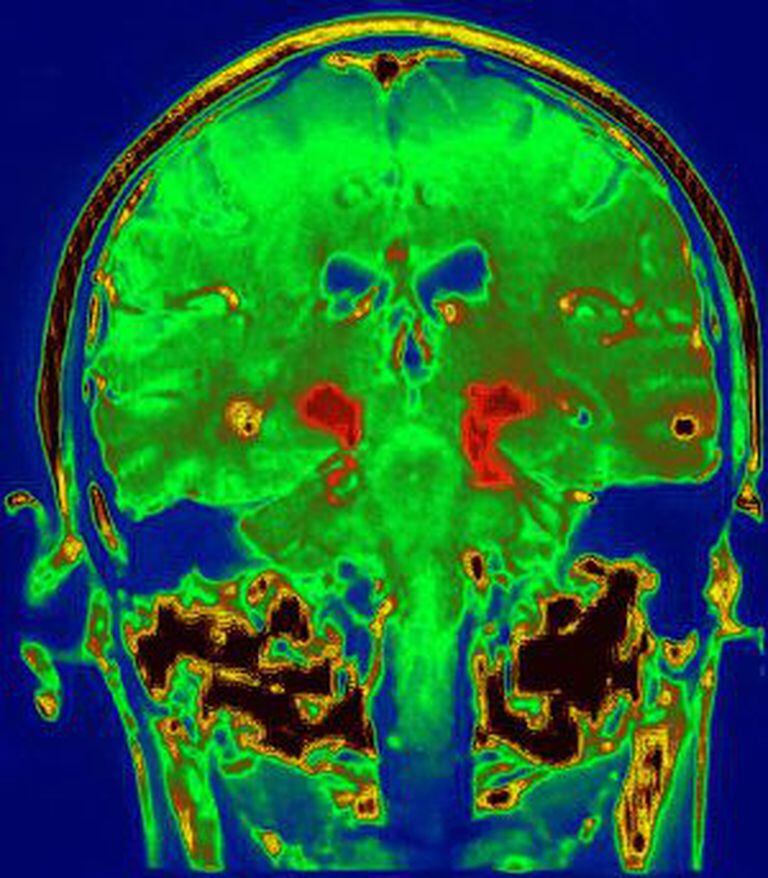

“Estudamos o cérebro após a morte em profundidade e com muitos detalhes. Mas, além disso, também acompanhamos a recuperação da funcionalidade dos demais pacientes, que estão vivos, e temos provas positivas, com imagens de PET [tomografia por emissão de pósitrons] de que os transplantes estão funcionando”, explica Isacson.